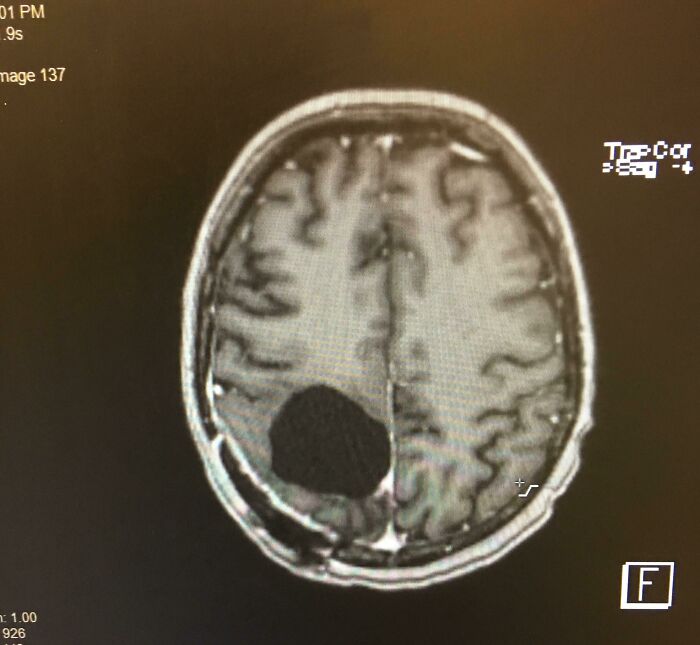

I Had A Brain Tumor Removed, And Now I’m A Bit Absent Minded